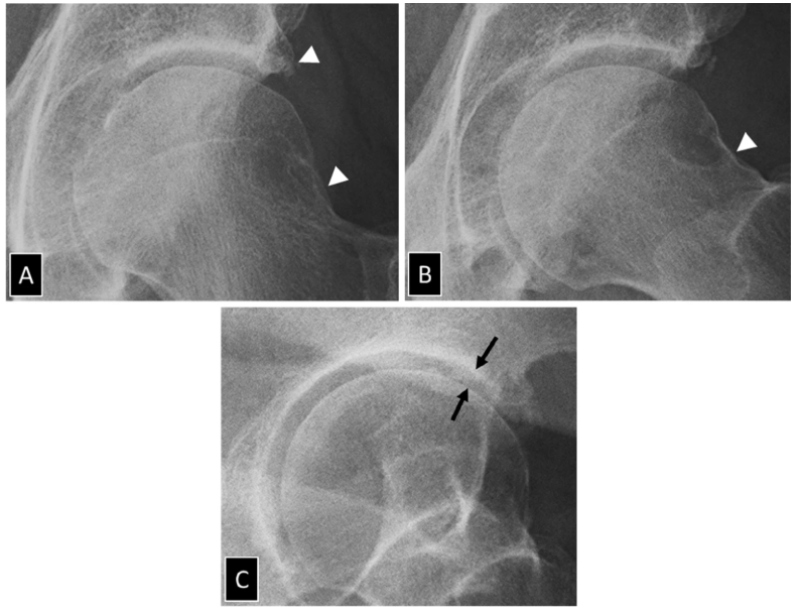

2 hình ảnh chụp X quang người đàn ông 65 tuổi sau 3 tháng. Hình A gai xương xuất hiện nhưng không có hẹp khe khớp, hình B khe khớp bị hẹp và xơ cứng dưới sụn

Giai đoạn 2 – Nhẹ: Hẹp khe khớp, hình thành gai xương rõ rệt và cứng xương bên dưới sụn.

X Quang thấy hẹp khe khớp

Hình ảnh X-quang cho thấy hẹp khe khớp bên (2 mũi tên hình A), xơ cứng dưới sụn của mái ổ cối (dấu sao) và gai xương đầu xương đùi (mũi tên hình B)